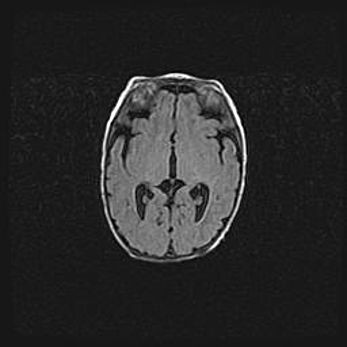

Ниже представлена  галерея МРТ снимков, полученных с применением LMT неонатальных матричных РЧ катушек. Также каждая группа МРТ снимков сопровождается информацией о пациенте (диагноз, возраст, вес, пол, срок гестации) и краткой сопроводительной расшифровкой диагноза.

Наружная гидроцефалия с возможной атрофией височных областей.

Возраст: 28 дней

Вес: 3670 г

Пол: мужской

Окружность головы: 38 см

Срок гестации: 40 недель

Гидроцефалия головного мозга у новорожденных – это заболевание, которое характеризуется скоплением избыточного количества спинномозговой жидкости в желудочковой системе головного мозга в результате затруднения её перемещения от места выработки к месту поглощения в кровеносную систему или вследствие нарушения абсорбции. При открытой наружной форме гидроцефалии у новорожденных расширяются и переполняются субарахноидные пространства.

При нормотензивных  формах,  которые,  как  правило,  являются  следствием  перенесенных ишемических  повреждений  паренхимы  мозга,  возможно  сочетание микроцефалии  с нормотензивной гидроцефалией. В основе данных изменений лежит атрофия больших полушарий с преимущественной  локализацией  в  лобно-височных  областях.